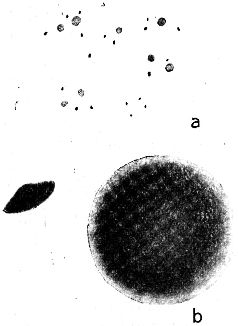

Abb. 1.

Die Hauptformen der Bakterien, schematisch. a Kugelbakterien (Kokken), b Stäbchenbakterien (Bazillen), c Schraubenbakterien (Spirillen).

Abb. 2

Abb. 2.

Ausstrichpräparat von menschlichem Zahnschleim, gefärbt, etwa 1000fach vergrößert. Mannigfaltige Bakterien in buntem Gemisch.